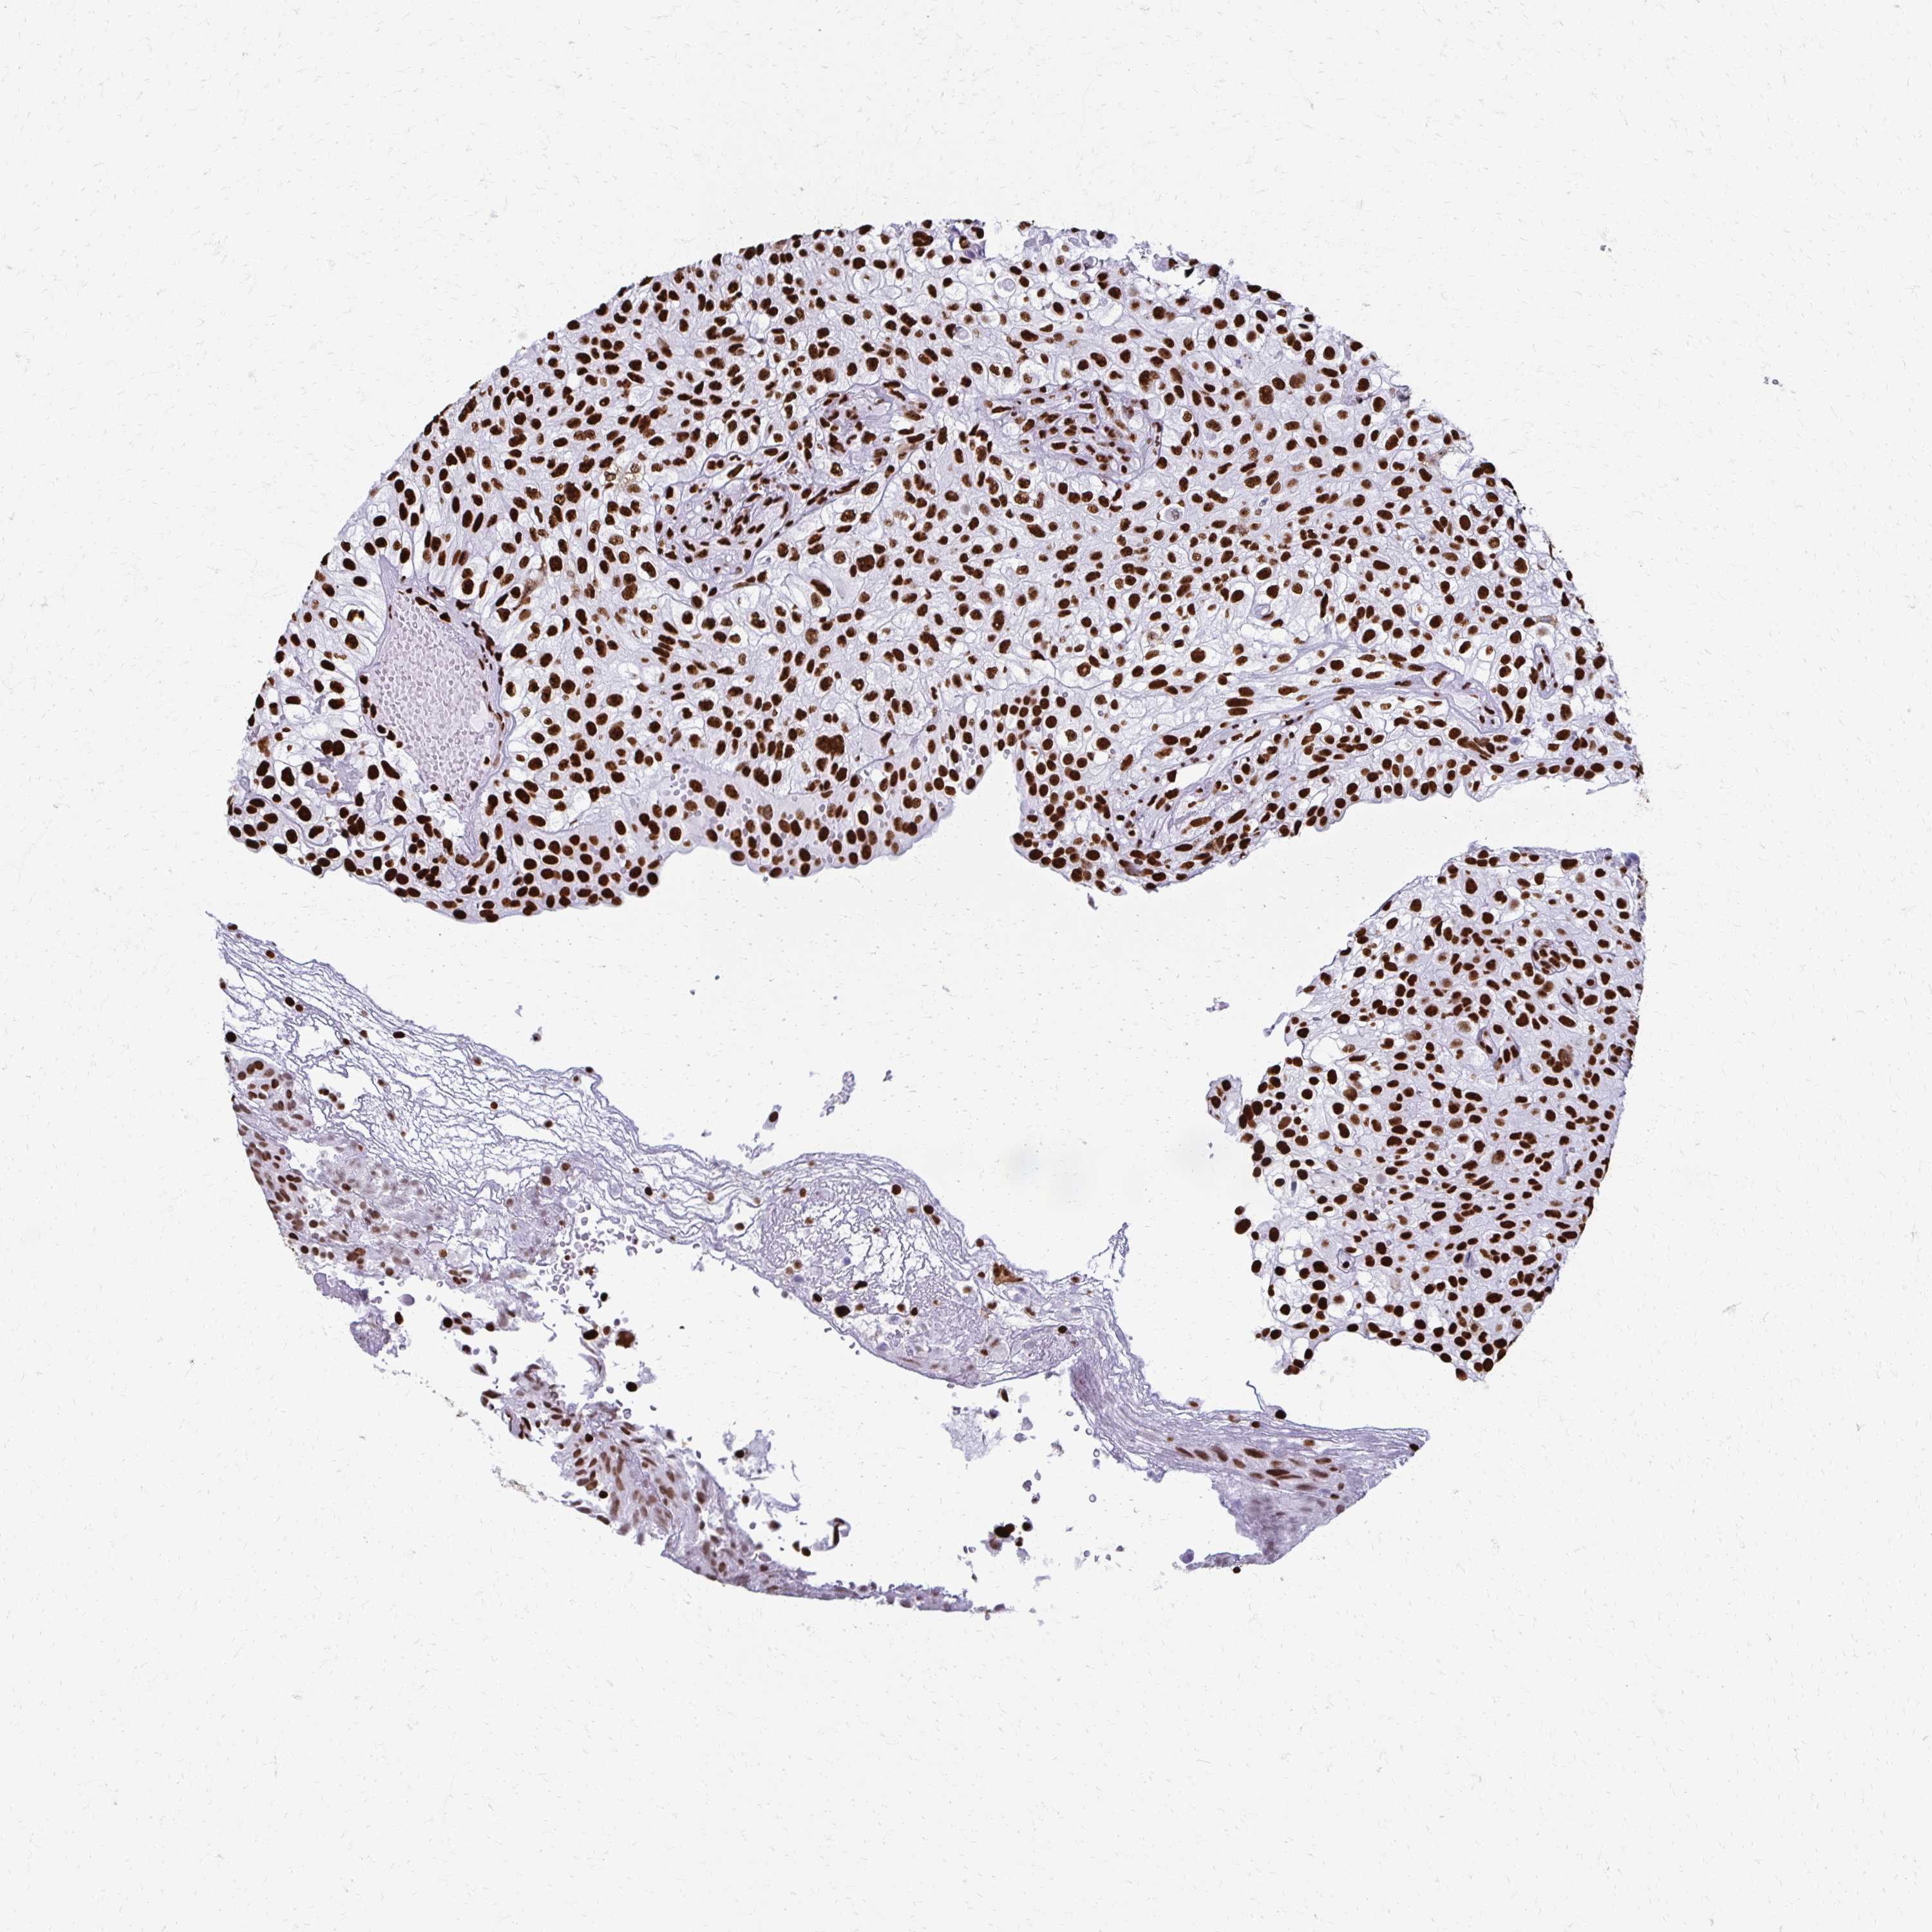

UROTHELIAL CANCER - Protein expressioni

A mouse-over function shows sample information and annotation data. Click on an image to view it in a full screen mode. Samples can be filtered based on level of antibody staining by selecting one or several of the following categories: high, medium, low and not detected. The assay and annotation is described here.

Note that samples used for immunohistochemistry by the Human Protein Atlas do not correspond to samples in the TCGA dataset.

Antibody stainingi

Antibody staining in the annotated cell types in the current human tissue is reported as not detected, low, medium, or high, based on conventional immunohistochemistry profiling in selected tissues. This score is based on the combination of the staining intensity and fraction of stained cells.

Each image is clickable and will lead to virtual microscopy that enables deeper exploration of all samples and also displays staining intensity scores, fraction scores and subcellular localization as well as patient and tissue information for each sample.

Antibody HPA054094

Antibody HPA054559

Antibody CAB022069

Staining

High

Medium

Low

Not detected

Intensity

Strong

Moderate

Weak

Negative

Quantity

>75%

75%-25%

<25%

None

Location

Nuclear

Cytoplasmic/membranous

Cytoplasmic/membranous,nuclear

Urothelial carcinoma, High grade

Urothelial carcinoma, NOS

Urothelial carcinoma, Low grade